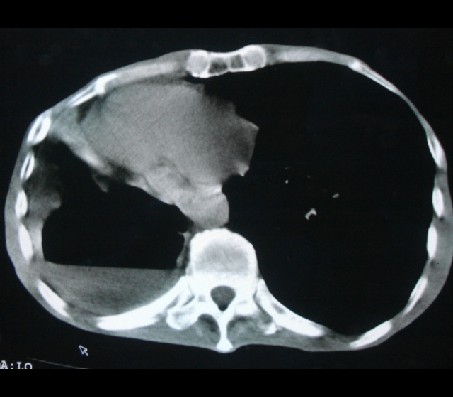

标题: CT17018:肺脓肿?左侧胸腔积液?请会诊! [打印本页]

男性,65岁,有肺结核病史。

我个人意见:右侧考虑肺部感染,肺脓肿可能,胸穿穿出了脓性液体。

1)两肺继发性肺结核,右肺多发空洞形成并感染,伴左肺支气管播散。2)右侧胸膜增厚、粘连。3)纵隔疝(左→右)。

1)两肺继发性肺结核伴右肺毁损,右肺多发空洞及肺大泡形成并感染,伴左肺支气管播散。右侧液气胸.2)右侧胸膜增厚、粘连。3)纵隔疝(左→右)。

右侧液气胸。

右下肺结核伴右肺空洞。

液气胸,毁损肺。老结核,纵隔疝。